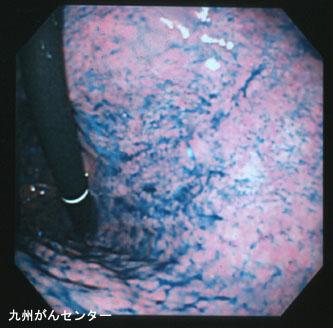

症例提示(所在地,施設名等): 福岡県・ 九州がんセンター

疾患(病理主体)の分類悪性上皮性腫瘍/印環細胞癌

部位(臓器別)胃(部位)/体部

検査方法内視鏡

腫瘍の肉眼分類0型(表在型)/IIb型(IIb)

病変の最大径(ミリ)20〜24

腫瘍の深達度m